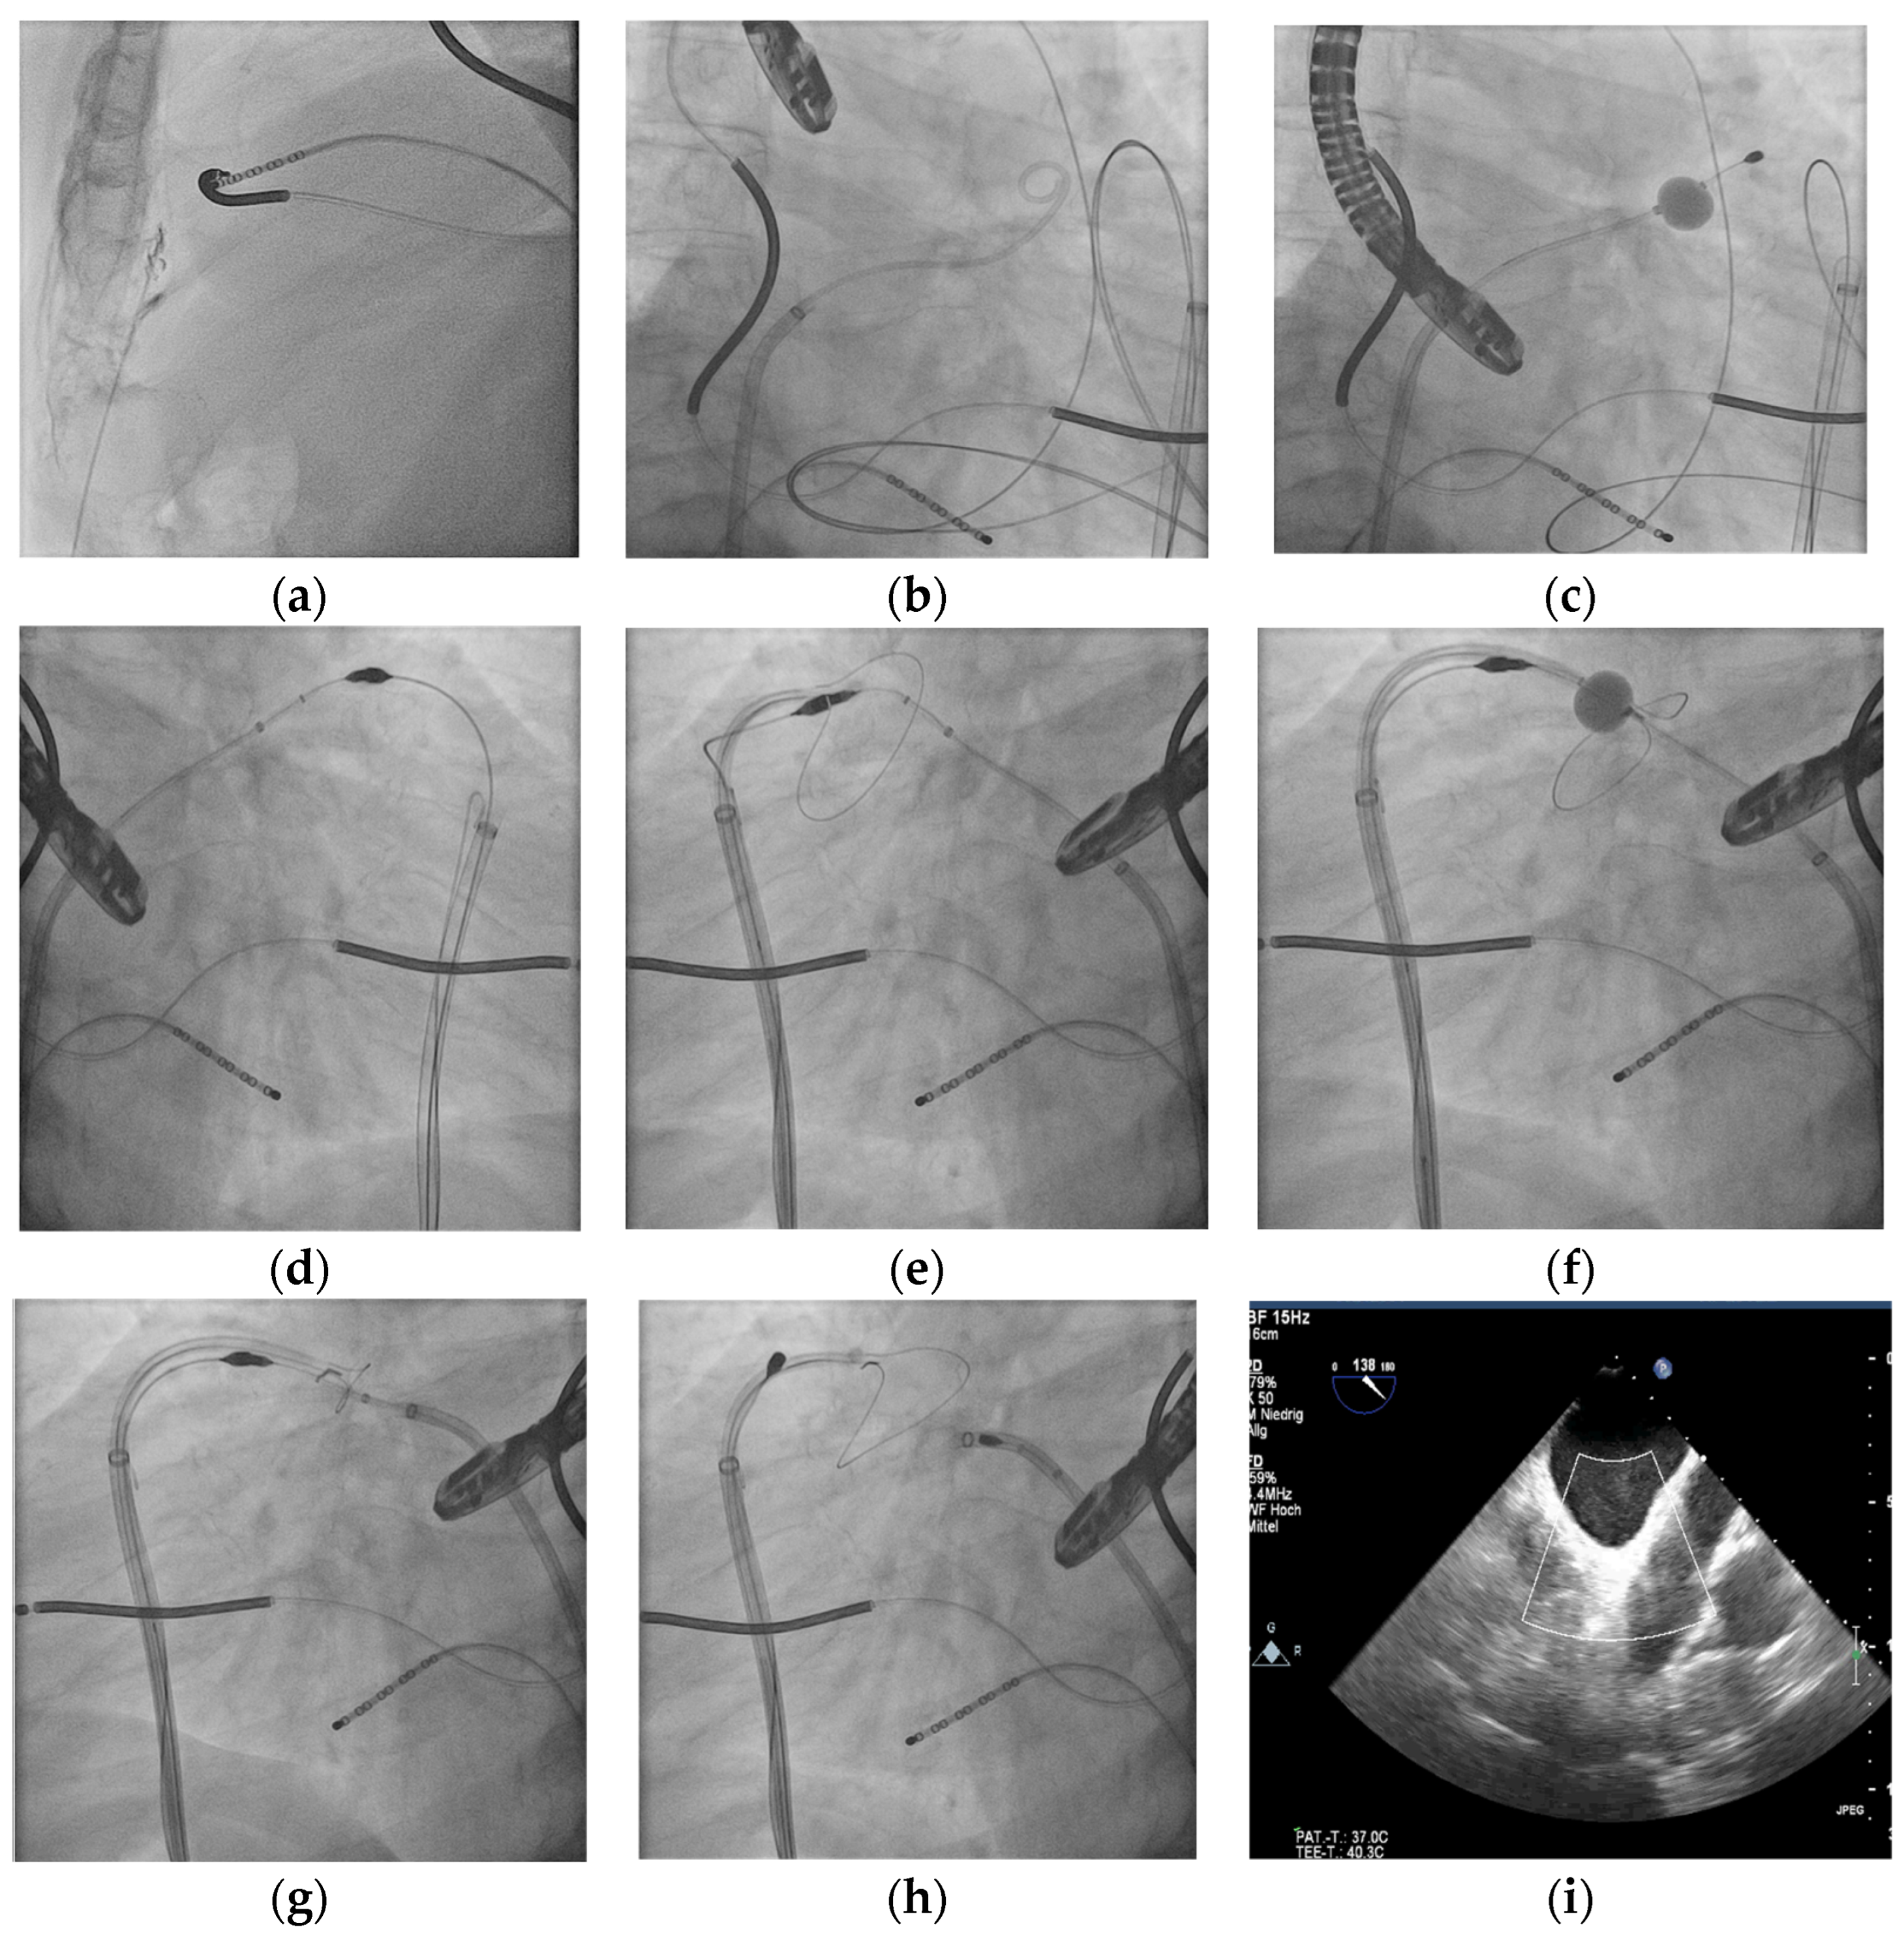

2.2. Procedure

3.1. Procedure